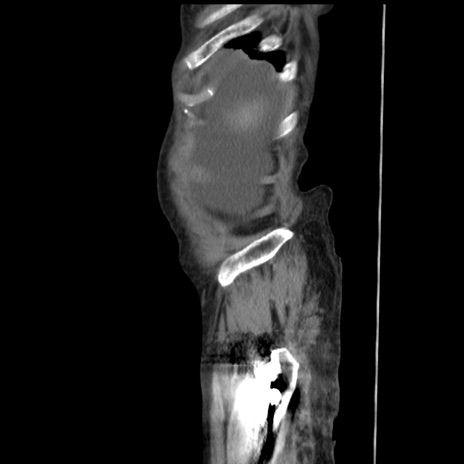

横断像

冠状断像